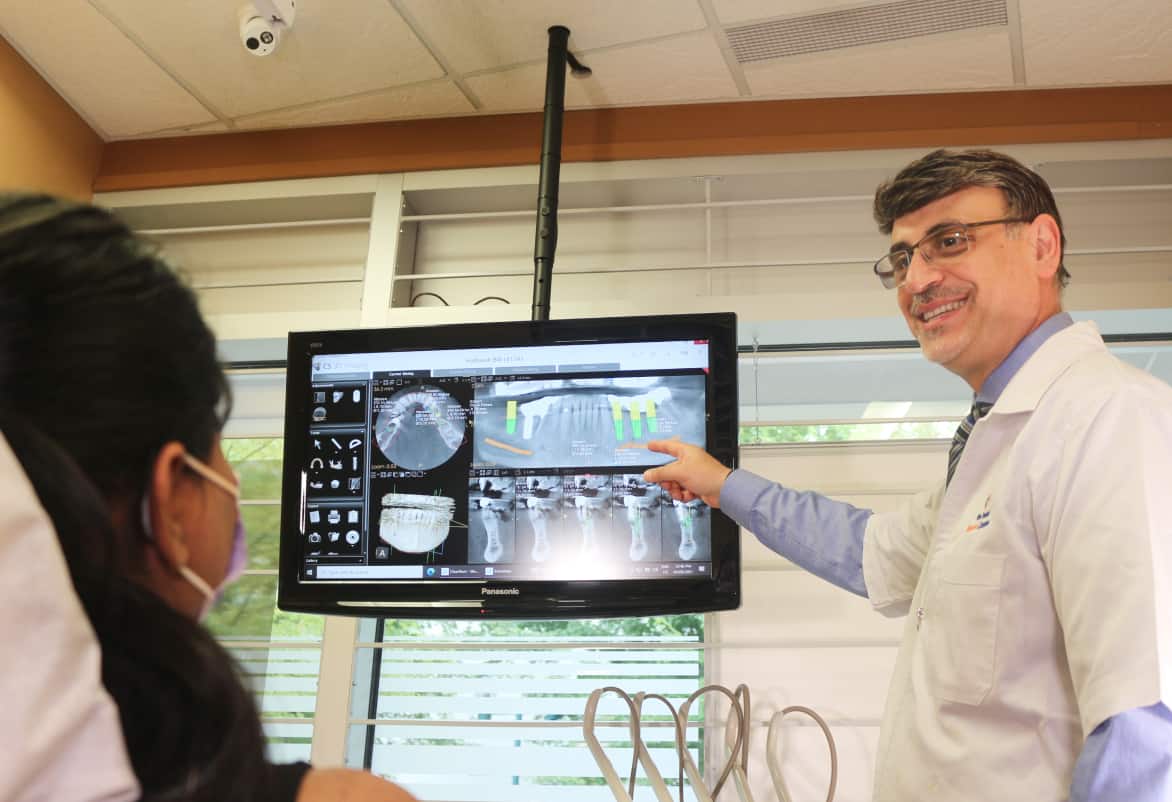

If you’re investing in implant supported dentures, you demand excellence for your smile.

Dr. Ashnaei knows that, and your vision of excellence is the measure he holds himself up to. With nearly 30 years of restorative dentistry experience, his approach brings together modern tools, proven techniques, and an artist’s touch - all focused on renewing your smile.